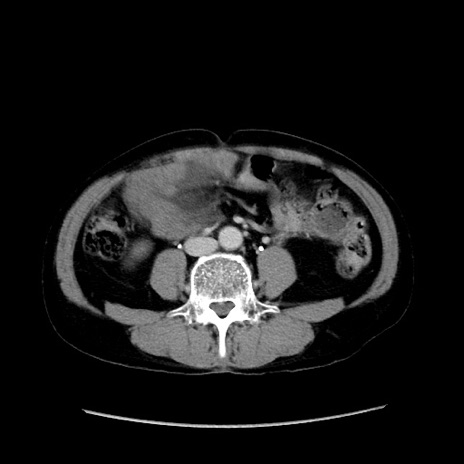

症例37(横断像)

【症例】40歳代 男性

【主訴】腹痛

【現病歴】4時間ほど前に電車に乗車中に臍部上より腹痛出現。徐々に増悪し起立困難となり、救急外来受診。生ものは数日食べていない。今朝お雑煮を食べた。

【身体所見】BT 36.8℃、BP 117/84mmHg、HR 91/min、SpO2 97%、苦悶様、腹部:臍上部広範囲圧痛あり、反跳痛±

【データ】WBC 8100、CRP 0.03